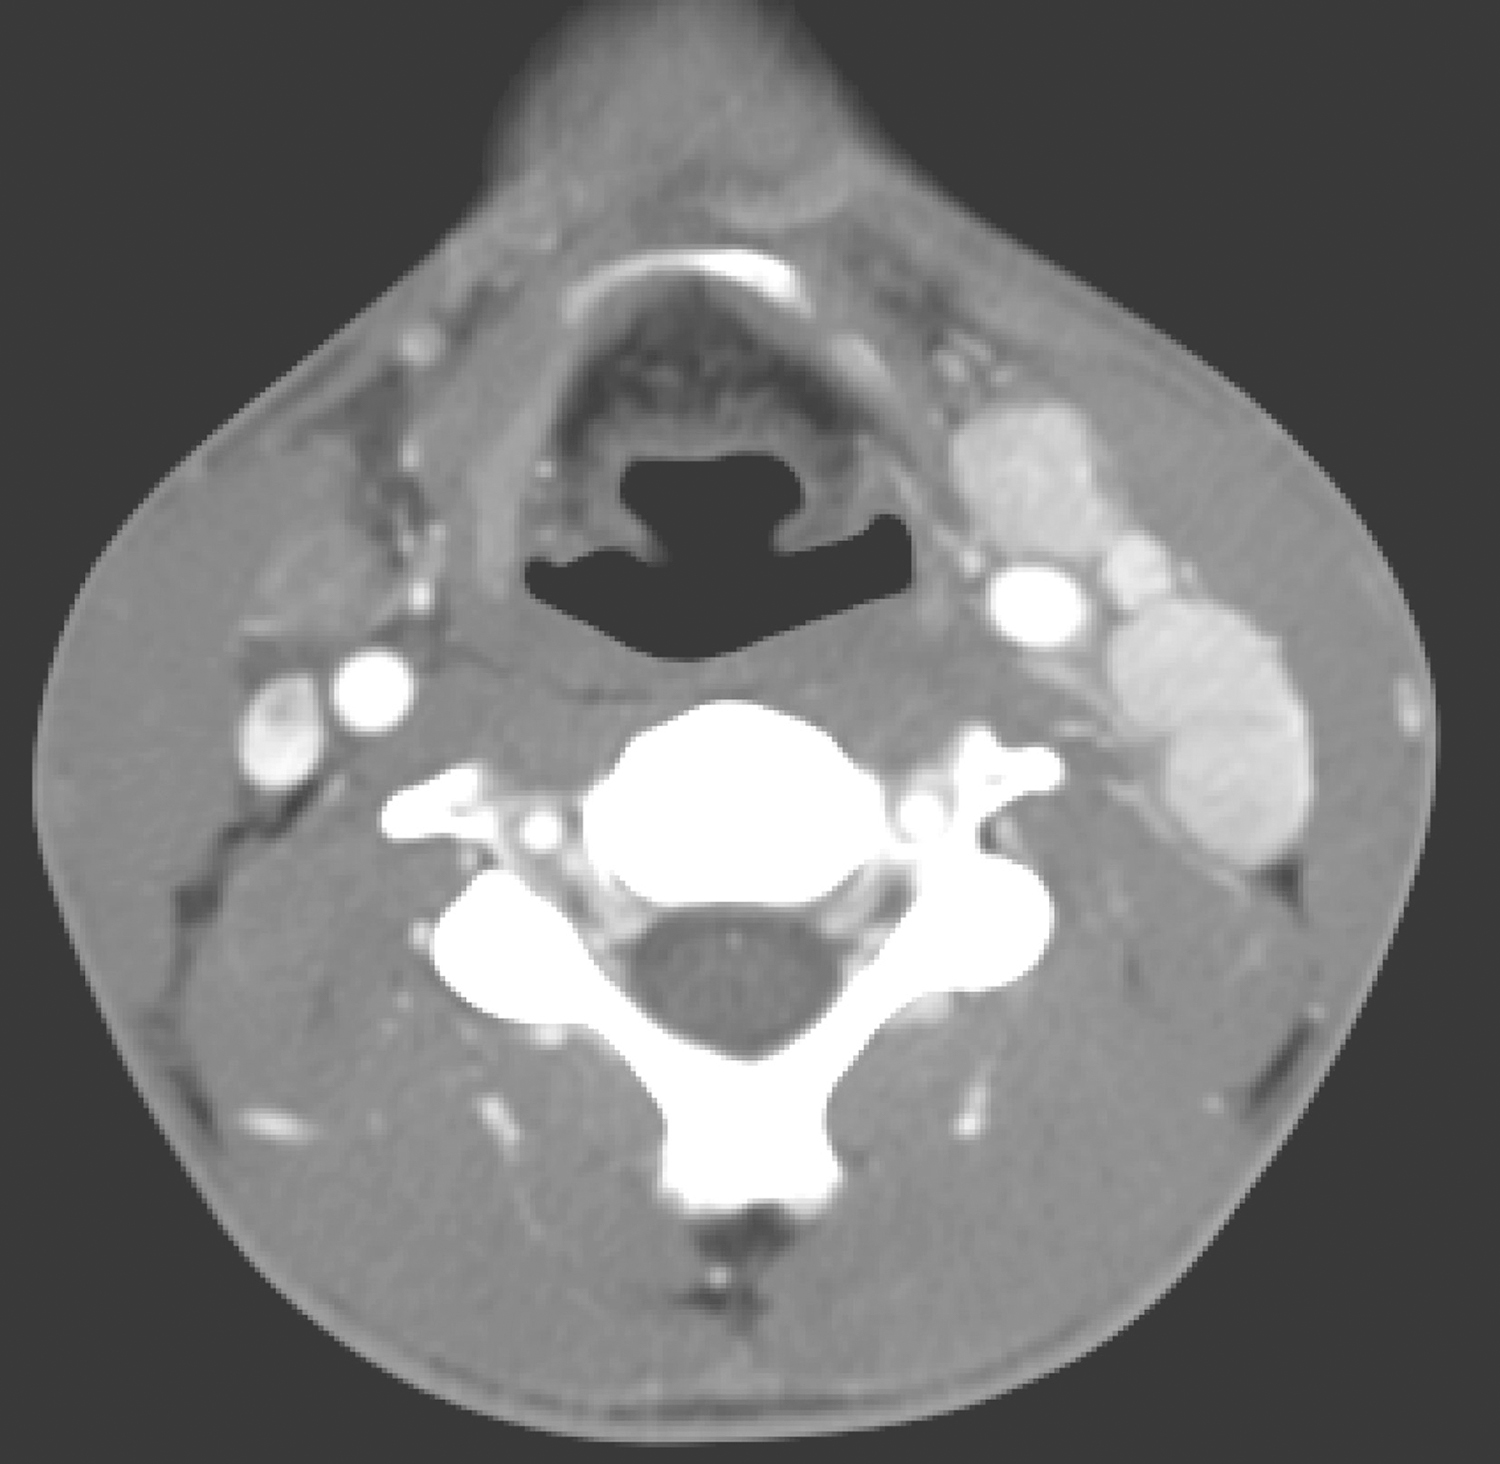

双侧颈深组、锁骨上及双侧气管食管沟多发肿大淋巴结,较明显强化(图3),大者短径约1.5cm。

图3 颈部增强CT示双侧颈多发肿大淋巴结